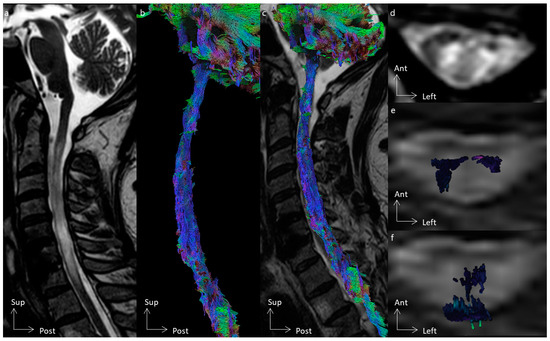

3.2. Tractography Rendering

4.2. The Added Value of Tractography